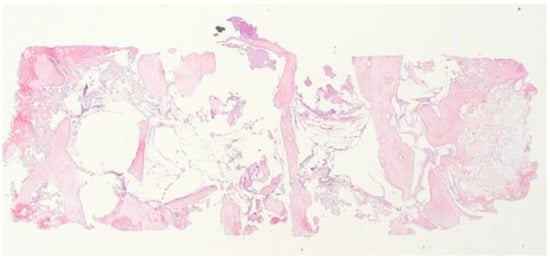

2.3. Histological Analysis